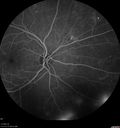

50 year old man: The patient noticed a few days ago, when putting on Contact Lenses for work which were slightly different from his usual strength. He therefore had some trouble at work with the new contact lenses. Then he had some haze in his vision. In the morning he went to see his mother in Venice and there was a new big black line in the left eye when he was getting up from lying down (this was yesterday). Then he noticed a lot of floaters in his vision that looked like blood. This has been fluctuating. You saw him this morning and asked him to come here. VA OD: Dcc20/20-2 NscJ1+ The patient has type I diabetes diagnosed at age 24 and he is now 50 years old VA OS: Dcc20/25+2 NscJ1+ IOP: TP: OD:17 OS:19

PDR and Vitreous Hemorrhage - High Risk Left Eye - Low Risk Right Eye412 views50 year old man with type I diabetes mellitus for 26 years. New Vitreous Hemorrhage in the left eye. Both eyes have NVE. Both also have foveal hypoplasia00000